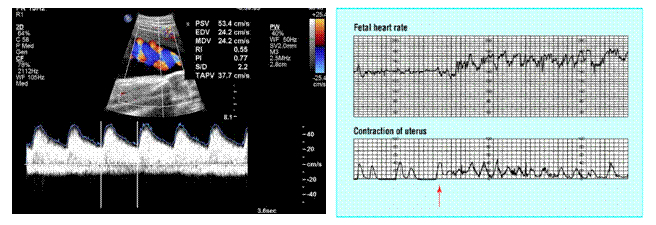

2) Υπερηχογράφημα Doppler: Είναι ένα υπερηχογράφημα Doppler αγγείων που μετράει τη ροή αίματος στον ομφάλιο λώρο για να διαπιστωθεί εάν ο πλακούντας τροφοδοτείται επαρκώς ή αν υπάρχουν σημάδια πλακουντιακής ανεπάρκειας και ενδομήτριας καθυστέρησης της ανάπτυξης.

2) Καρδιοτοκογράφημα (NST): Είναι μια εξέταση που βλέπουμε τη δραστηριότητα της μήτρας, εάν κάνει συσπάσεις ή όχι, και την κινητικότητα του μωρού. Αυτή η εξέταση συστήνεται κατά περίπτωση.